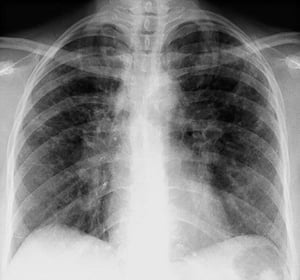

Sarcoidosi (stadio II)

Adenopatie ilari bilaterali con opacità interstiziali nella sarcoidosi al II stadio.

By permission of the publisher. Da Tanoue L, Elias J. In Bone's Atlas of Pulmonary and Critical Care Medicine. Edited by J Crapo. Philadelphia, Current Medicine, 2005.